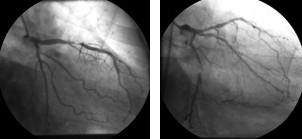

Stenosi ramo discendente anteriore e stenosi ramo circonflesso

L’intervento di bypass che tecnicammente afferisce alla rivascolarizzazione miocardica consiste nell’eseguire uno o più innesti a ponte tra l’aorta ascendente e le arterie coronarie o tra un’arteria sistemica ed il ramo coronarico, superando cosi’ l’ostruzione coronarica. Ai fini della valutazione dell’entita’ della patologia coronarica, si parla di stenosi significativa quando si ha una stenosi coronarica superiore o uguale al 70%, se i vasi coronarici sono la discendente anteriore, la circonflessa, e la coronaria destra, se si tratta del tronco comune allora la stenosi deve essere superiore al 50%.